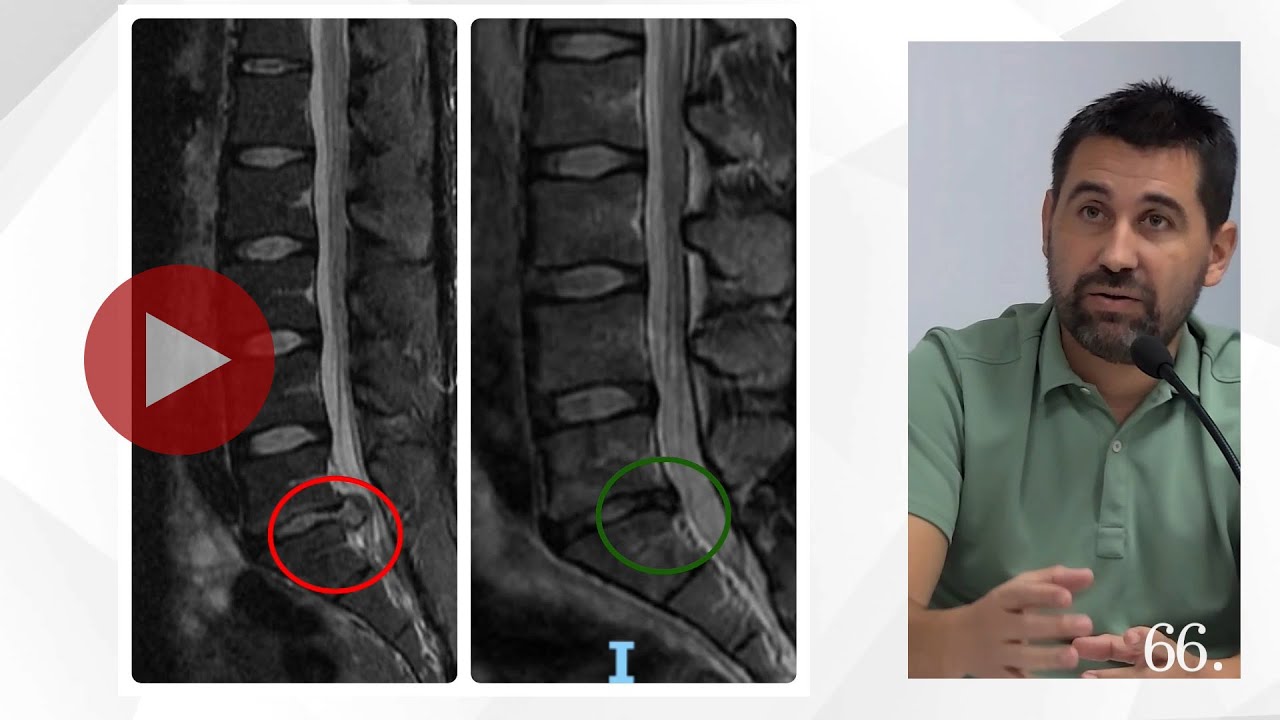

La bomba diamagnètica per a tractar les hèrnies discals